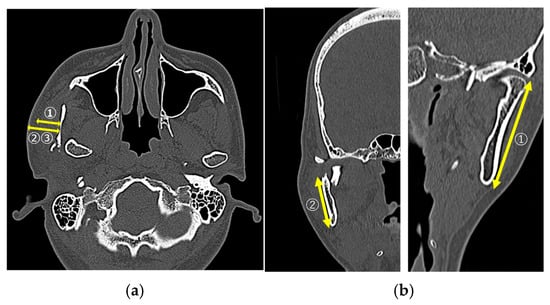

Figure 1

Background: The high perimandibular approach (HPA) is a feasible surgical technique for open reduction and internal fixation (OR-IF) of mandibular condylar fractures, offering reduced complication rates. In this study, we retrospectively evaluated the treatment outcomes and complications associated with HPA use. Patients and [...] Read more.

Background: The high perimandibular approach (HPA) is a feasible surgical technique for open reduction and internal fixation (OR-IF) of mandibular condylar fractures, offering reduced complication rates. In this study, we retrospectively evaluated the treatment outcomes and complications associated with HPA use. Patients and Methods: Patients who underwent OR-IF for mandibular condylar fractures using the HPA at three hospitals in Shimane between June 2019 and March 2024 were included. Data collected included the mechanism of injury, AO classification of the fracture site, fracture type and mode, surgical duration, mouth-opening range at 6 months post-operatively, and peri- and post-operative complications. Results: A total of 42 patients (46 condylar fractures; 18 males and 24 females; mean age, 63.0 years) were included. The fracture pattern included dislocations in 18 cases (42.8%). The mean surgical duration was 75.0 min. Post-operative trismus occurred in 16 patients (38.1%) at 6 months. Longer surgical duration and dislocated fractures were significantly associated with post-operative trismus (p < 0.05). Conclusions: The HPA is safe and effective for managing mandibular condylar fractures. However, post-operative trismus may be influenced by longer surgical duration and fracture types, warranting further investigation and potential post-surgical management. Full article